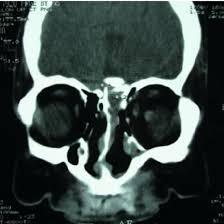

Medifyhome provides NCCT PNS Sagittal, which is a non-contrast computed tomography in a sagittal view of the paranasal sinuses. This is the imaging modality that provides comprehensive details on the paranasal sinuses without the use of any contrast media. Such a procedure will make use of advanced CT to deliver high-resolution images that help diagnose conditions like sinusitis, nasal obstruction, and other structural abnormalities. The sagittal view shows better visualization of the sinuses in their most complex anatomy, thus offering more accurate diagnosis and treatment planning. Medifyhome is committed to making this a smooth experience with well-equipped, up-to-date equipment to highly experienced radiologists who will ensure the imaging results are as close to reality as possible. Book your NCCT PNS Sagittal with Medifyhome today and get correct and complete diagnostic information about the status of your sinuses. Book an appointment today for your NCCT PNS Sagittal and get diagnosed right on time by visiting Medifyhome’s official website or contact us at +919100907036/+919100907622.

A Non-Contrast Computed Tomography PNS Sagittal scan is a modality of imaging that helps in the visualization of the paranasal sinus without the use of contrast. This non-invasive procedure gives detailed cross-sectional pictures of the sinus cavity and its surrounding structures and yields useful information about anatomy and possible abnormalities. The patient lies on a table during the scan, which traverses into and out of a CT scanner while the camera inside it rotates around the patient, taking numerous views of the structure from various angles. The sagittal view particularly outlines the complex anatomy of the sinuses to diagnose conditions such as sinusitis, nasal polyps, and other abnormalities. This is very useful in patients with possible allergies to contrast or issues with their kidneys and allows for a non-invasive modality to effectively evaluate the sinuses.